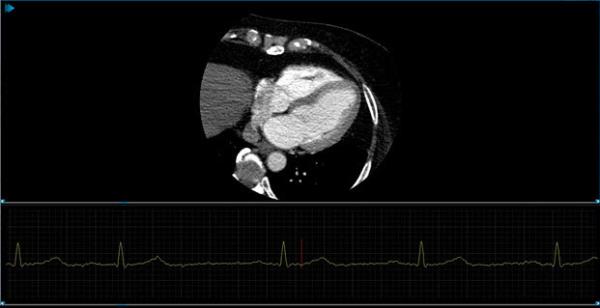

Non-symmetric 2x1-1/3 study layout with ECG view